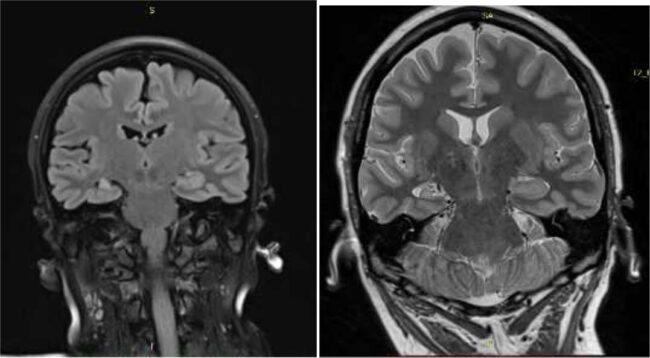

ეპილეფსიის ქირურგიული მკურნალობის დანერგვის ეტაპები

ნევროლოგიისა და ნეიროფფსიქოლოგიის ინსტიტუტისა და კავკასიის მედიცინის ცენტრის ეფექტური კოლაბორაციულლი ურთიერთთანამშრომლობის საფუძველლზე…